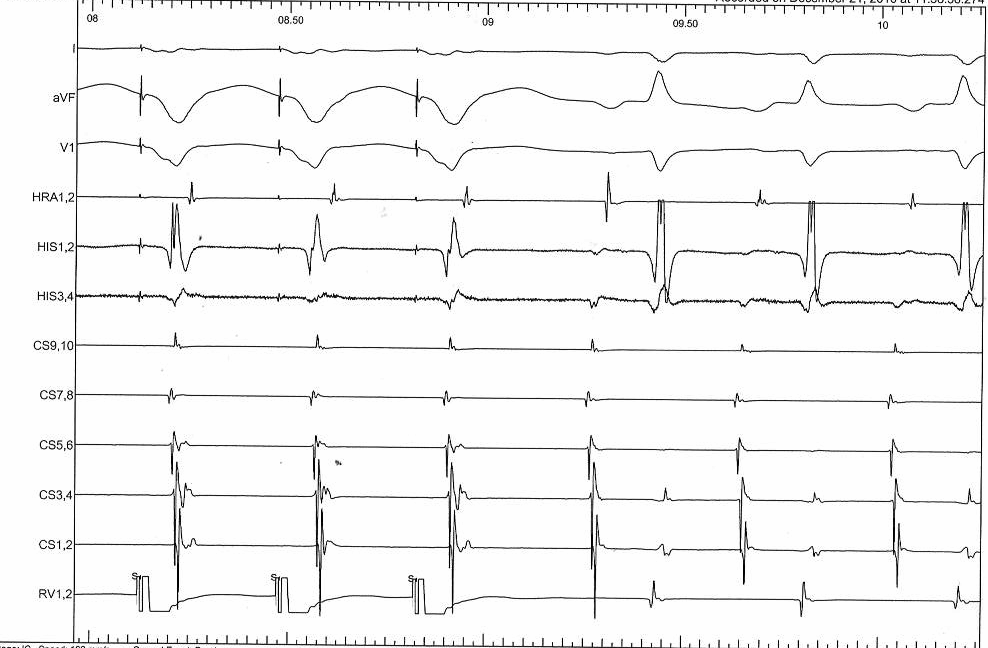

Differential pacing

• VA interval during pacing from apex and base

• Shorter from apex for nodal conduction

• Shorter from base for AP conduction

RV apex pacing

rv_apex_va.jpg

RV base pacing

rv_base_va.jpg